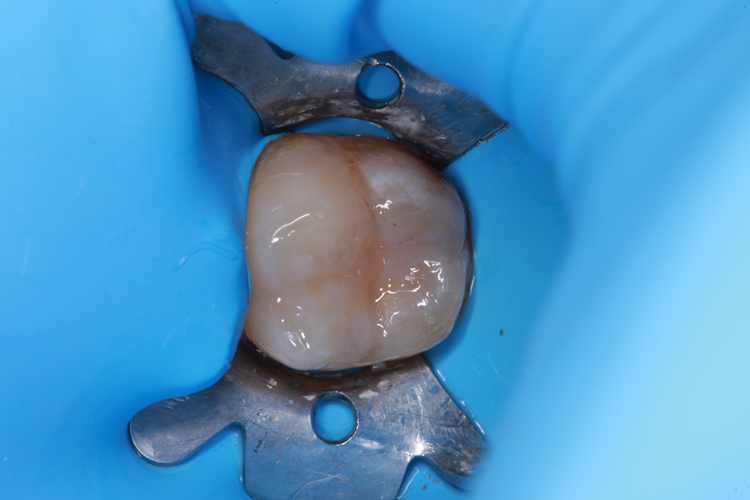

Technically, the procedure was very efficient. After the placement of rubber dam, the amalgam restorations (Fig. 1) and any signs of caries were removed (Fig. 2).

Fig. 1: Failed amalgam restoration. Fig. 2: Amalgam and decay are removed and tooth is prepared with ACTIVA BioACTIVE-RESTORATIVE.

ACTIVA BioACTIVE-RESTORATIVE was placed (Fig. 5) and, thanks to its dual cure capability, I did not have to worry about depth of cure in deep cavities. Figure 6 shows the completed restoration.

Fig. 5: Placement of ACTIVA BioACTIVE-RESTORATIVE. Fig. 6: Final restoration.